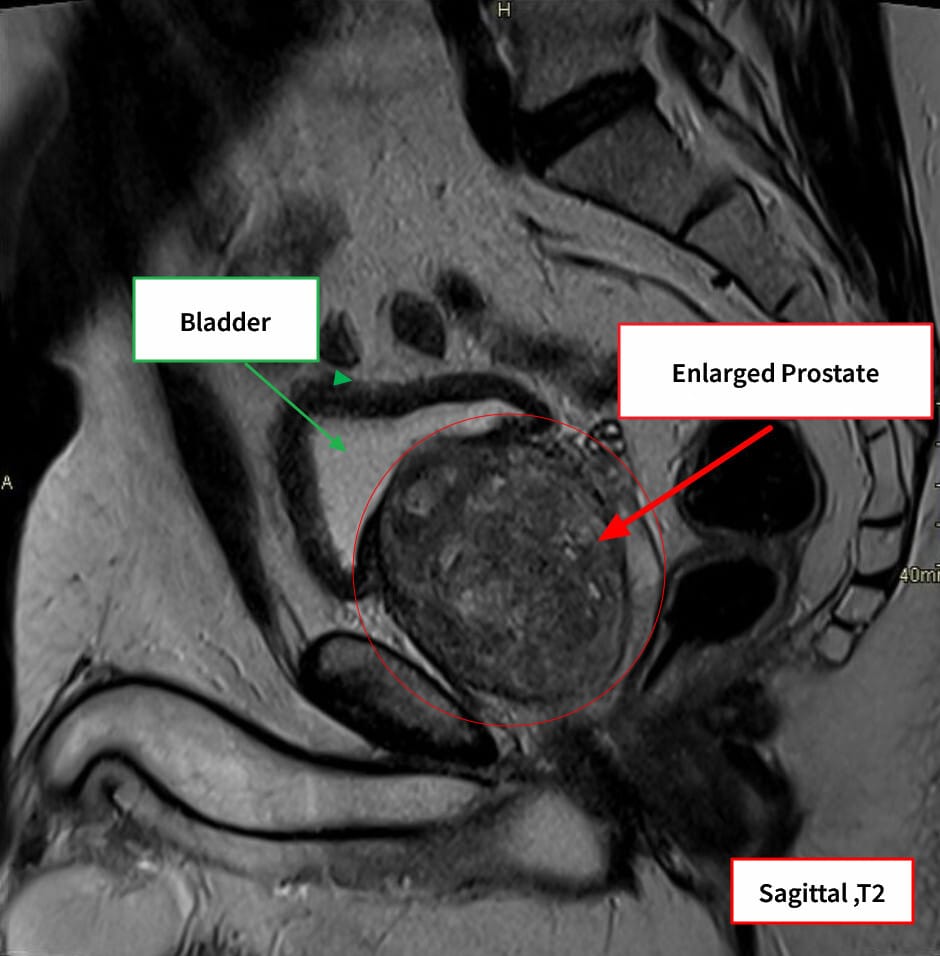

영상소견 정리

초음파 및 MRI에서 전립선 용적 증가와 중간엽(transition zone) 비대가 특징적입니다.

| 🔍 특징적 영상소견 요약 |

| ✅ 전립선 용적 증가 (≥30 mL) |

| 경직장 초음파에서 비대 확인 |

| ✅ 중심부 압박 및 요도 협착 |

| 중앙 요도를 압박하며 narrowing 보임 |

| ✅ 방광 잔뇨량 증가 |

| 비대에 의한 배출 장애로 잔뇨 발생 |

Bickle I, Benign prostatic hyperplasia. Case study, Radiopaedia.org (Accessed on 17 May 2025) https://doi.org/10.53347/rID-206343